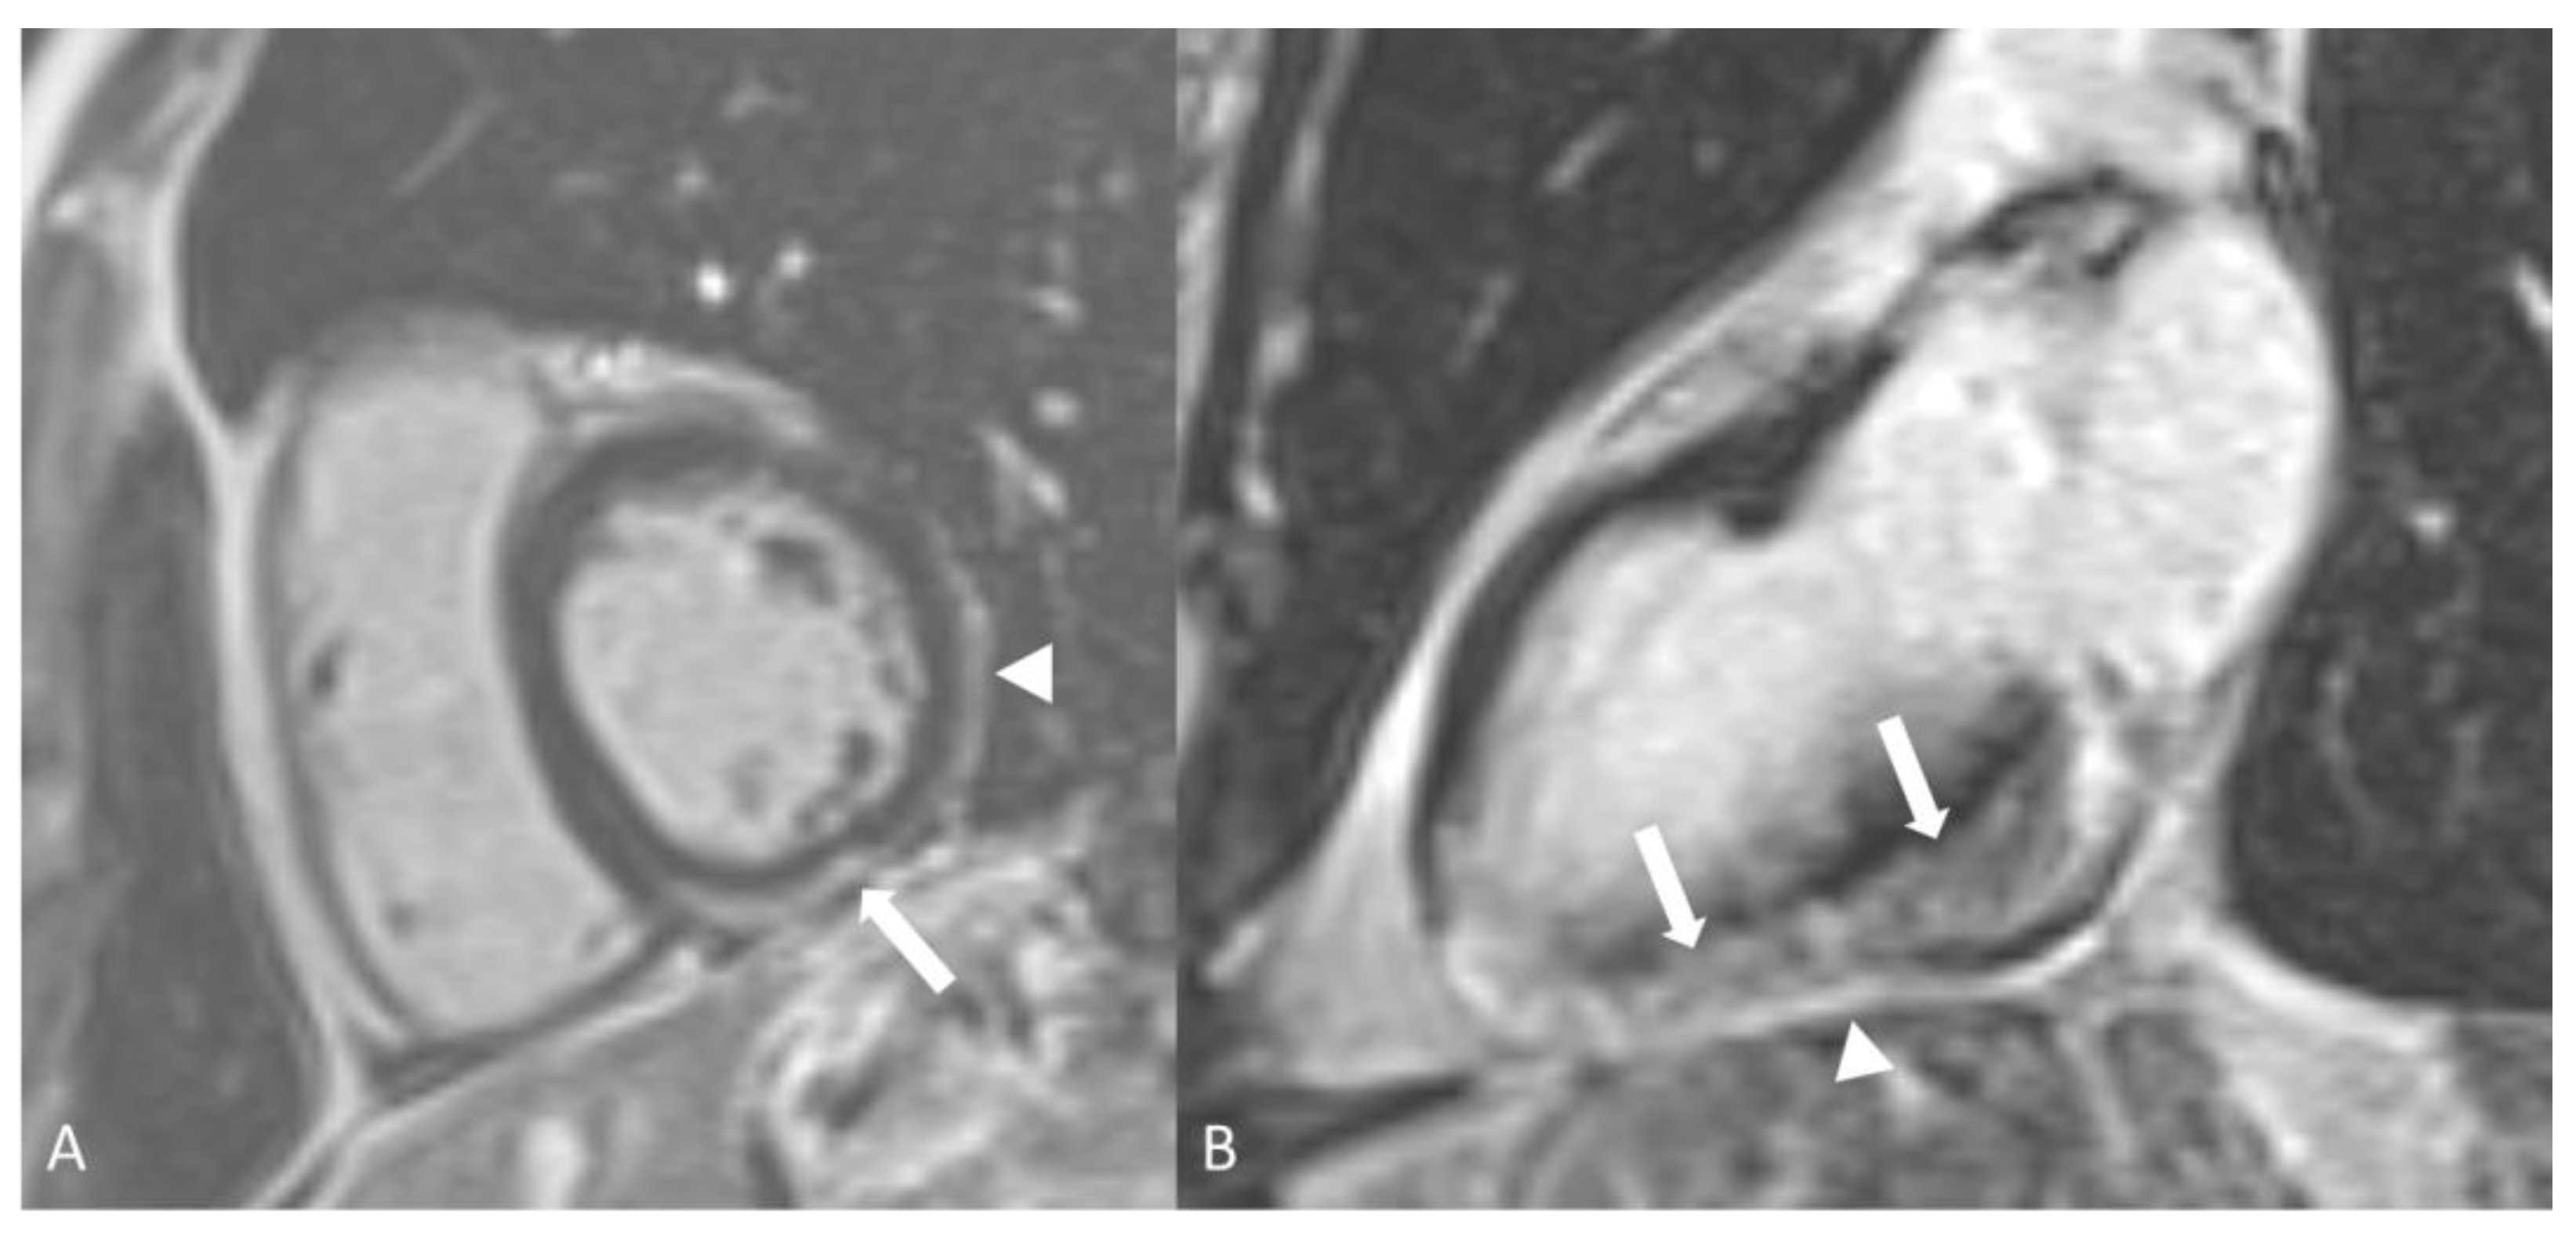

2.2.2. Kawasaki Disease

- Duarte, R.; Cisneros, S.; Fernandez, G.; Castellon, D.; Cattani, C.; Melo, C.A.; Apocada, A. Kawasaki disease: A review with emphasis on cardiovascular complications. Insights Imaging 2010, 1, 223–231. [Google Scholar] [CrossRef]

- Greil, G.F.; Stuber, M.; Botnar, R.M.; Kissinger, K.V.; Geva, T.; Newburger, J.W.; Manning, W.J.; Powell, A.J. Coronary Magnetic Resonance Angiography in Adolescents and Young Adults with Kawasaki Disease. Circulation 2002, 105, 908–911. [Google Scholar] [CrossRef]

- Dennert, R.M.; van Paassen, P.; Schalla, S.; Kuznetsova, T.; Alzand, B.S.; Staessen, J.A.; Velthuis, S.; Crijns, H.J.; Tervaert, J.W.C.; Heymans, S. Cardiac involvement in Churg-Strauss syndrome. Arthritis Rheum. 2010, 62, 627–634. [Google Scholar] [CrossRef]